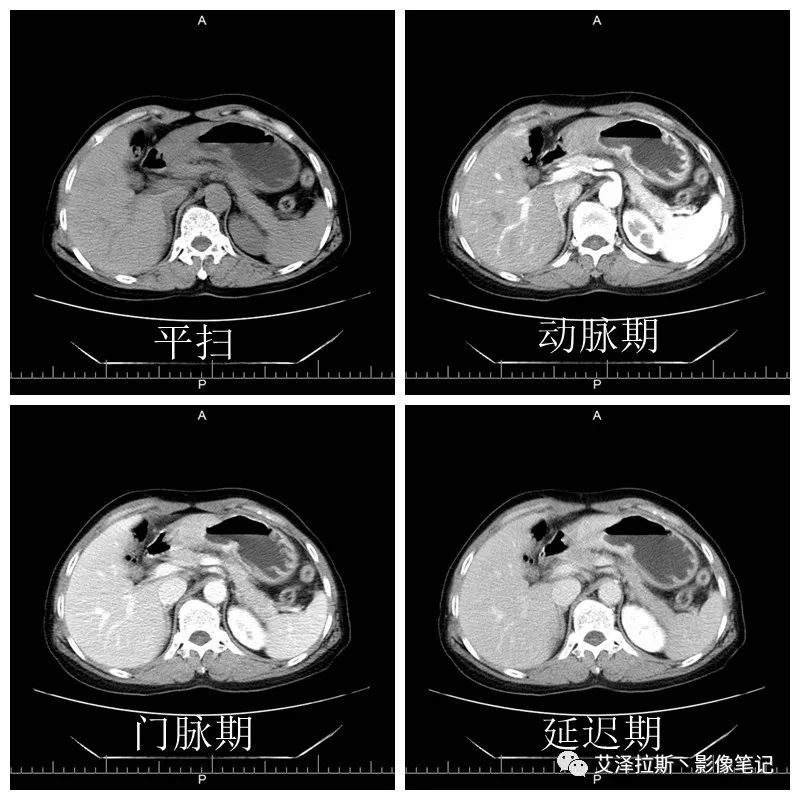

圖1 平掃+增強(qiáng)各期

【影像所見】 胃竇部狹窄,胃壁環(huán)形增厚,小彎側(cè)見一巨大潰瘍,周圍伴“環(huán)堤征”,漿膜面不完整,胃周脂肪見網(wǎng)格狀條索影,病灶與肝臟左葉、胰腺鉤突脂肪間隙消失,增強(qiáng)掃描病灶明顯強(qiáng)化。引流區(qū)內(nèi)約15個區(qū)域淋巴結(jié)受累。